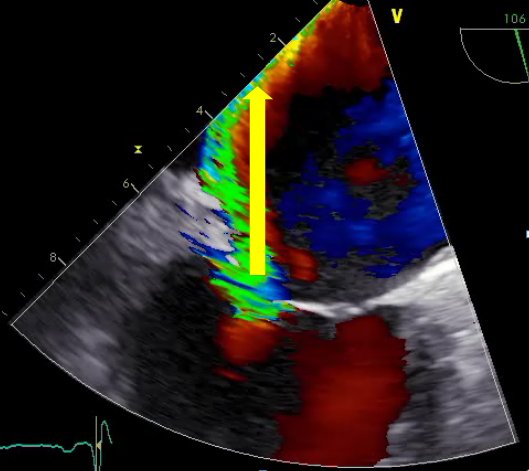

Auf den Bildern sehen Sie eine Echokardiografie vor (01), während (02) und nach (03) einer kathetergestützten Rekonstruktion der Mitralklappe mittels MitraClip®. Der große Pfeil zeigt eine ausgeprägte Undichtigkeit vor dem Eingriff (01). Der rote Kreis markiert die MitraClip-Implantation (02). Und der kleiner Pfeil verdeutlicht eine nur noch geringe Undichtigkeit nach dem Eingriff (03).